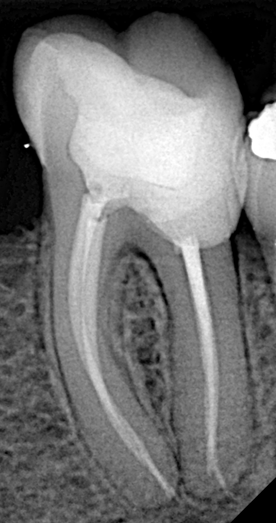

Postoperative Outcome

The procedure resulted in a well-shaped, thoroughly cleaned, and properly obturated root canal system. The patient reported complete resolution of symptoms following treatment.

This advanced root canal treatment case proves that even molars with extremely long canals (up to 27mm) and additional complexities like a lateral foramen can be managed successfully with the right instruments and protocol.

Dr. Othman H. Alani’s meticulous approach — from precise access and length measurement to flexible shaping and activated irrigation — highlights how modern endodontic tools enable predictable outcomes in anatomically difficult cases.